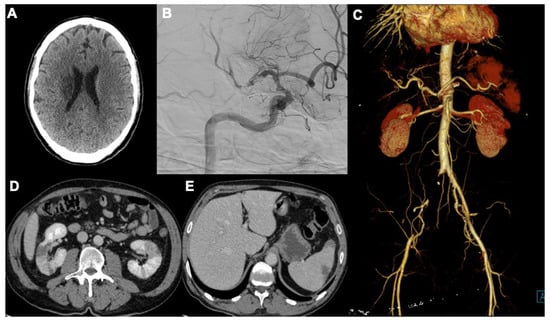

3.1. Neurological Findings

3.2. Cardiac Manifestations